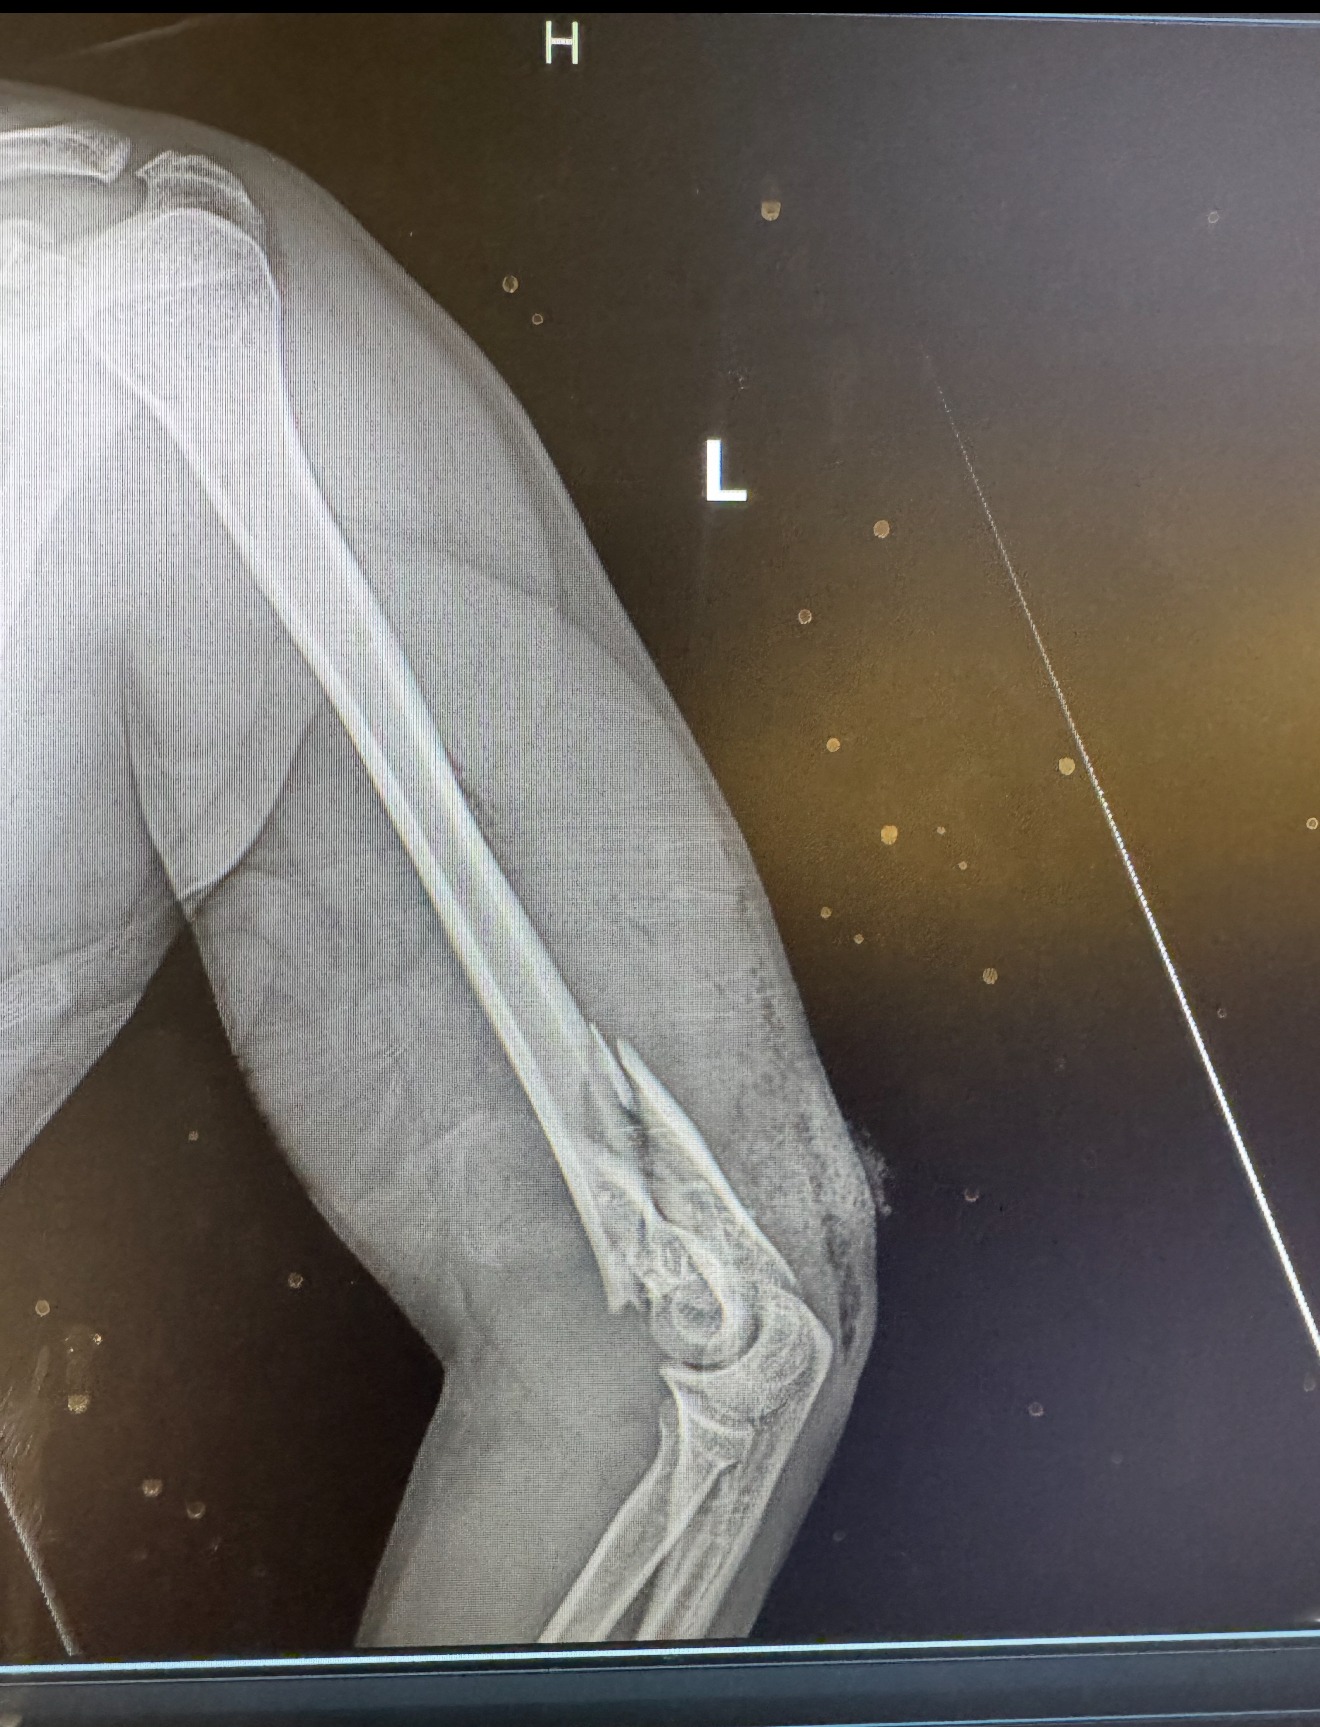

On September 1st, our dear friend Edwin Marques was involved in a devastating accident. While riding his bicycle, he was struck by a motorbike at full speed. The impact threw him to the ground and resulted in serious injuries ,a broken left arm, fractures in his hip and leg, and severe bruising across his body.